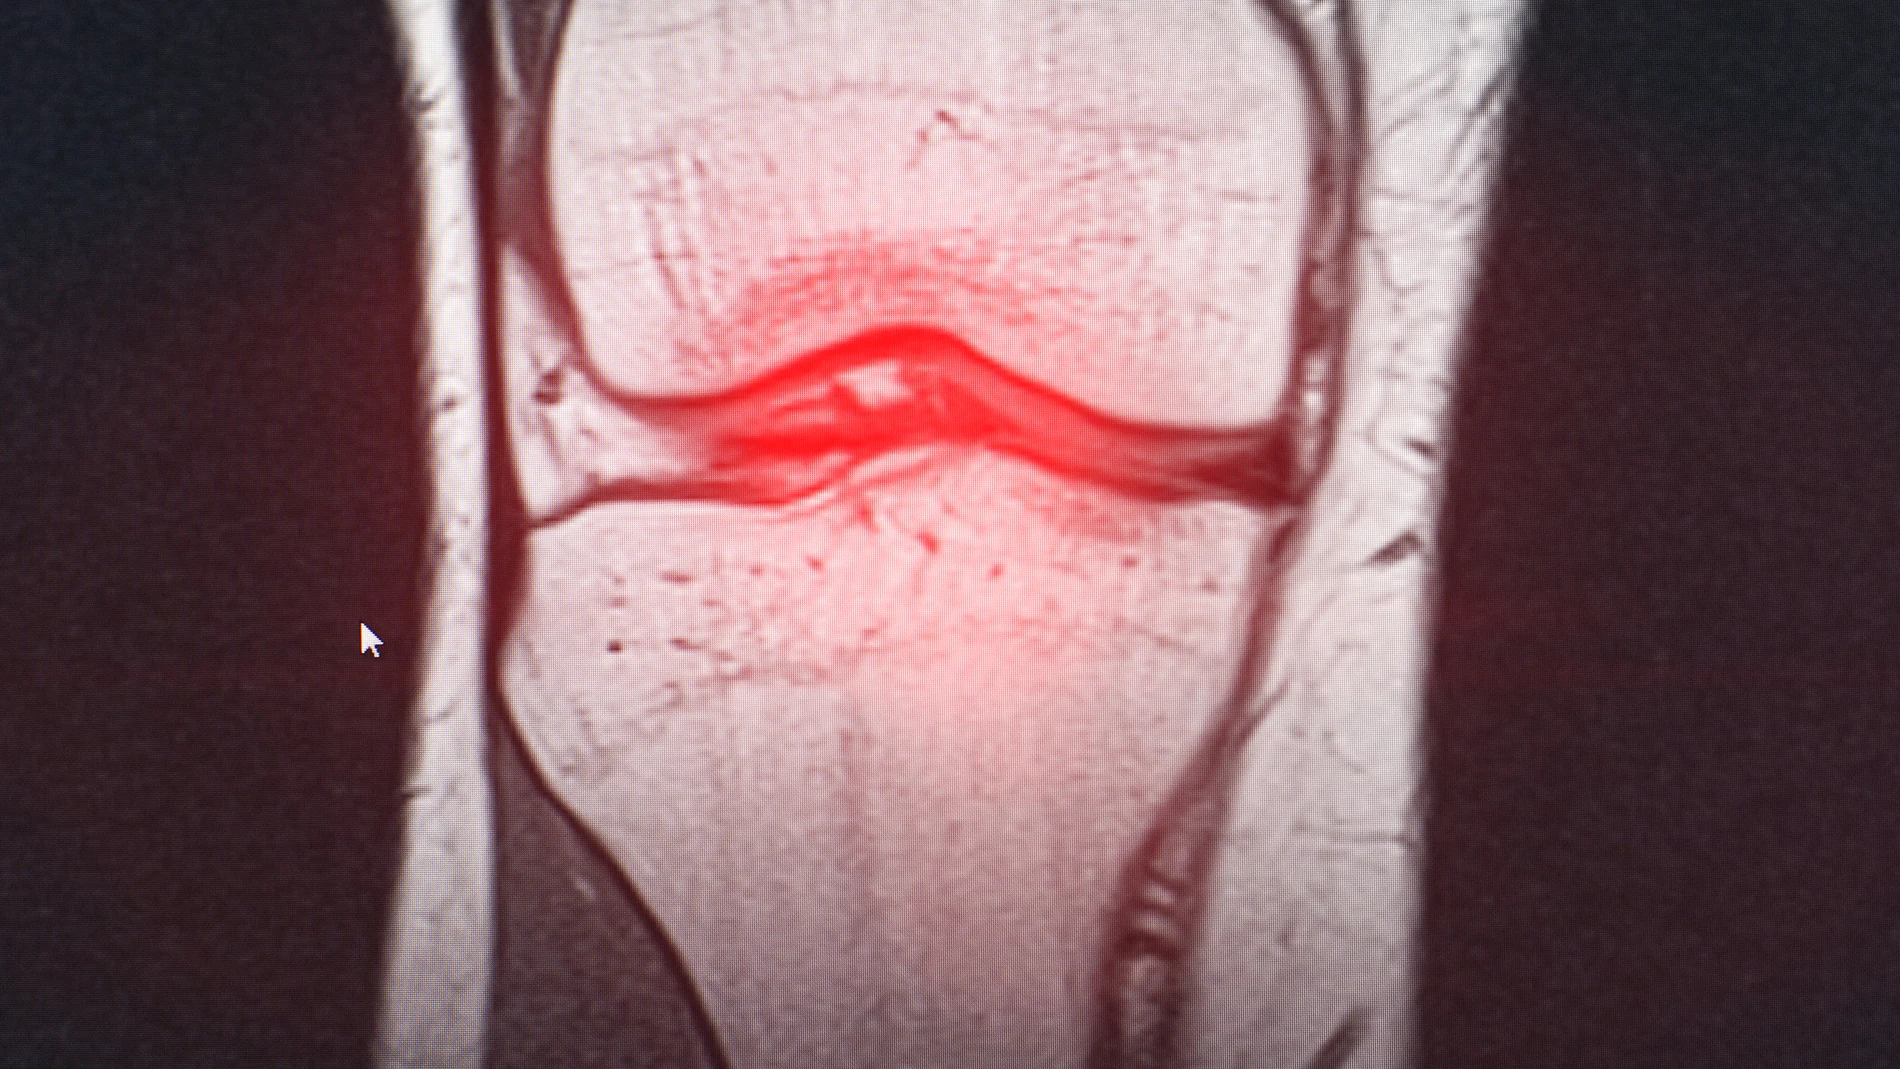

Consiguen mejorar la artrosis de rodilla con una única dosis de ácido hialurónico

Un trabajo español confirma la eficacia de este tratamiento al conseguir reducciones del dolor que han oscilado entre el 32% y el 40% respecto al valor inicial registrado

Un estudio reumatológico ha confirmado la eficacia del tratamiento de la artrosis de rodilla con una única dosis de ácido hialurónico. La investigación en el tratamiento de esta patología, realizada por un grupo de reumatólogos de diversos hospitales españoles, ha demostrado la eficacia de administrar una sola inyección intraarticular en la rodilla, mediante la nueva formulación de viscosuplementación con MPS-HA2%, después de haber trascurrido 12 meses desde la inyección.

En esta investigación se ha tratado de evidenciar el beneficio que puede generar el ácido hialurónico intraarticular en los pacientes artrósicos con comorbilidades, y que presentaban respuestas desfavorables a otros tratamientos farmacológicos. En general, el ácido hialurónico suele ser suministrado en ciclos de entre tres y cinco inyecciones, pero la tendencia que se busca ahora es reducir el número de pinchazos de manera que se mantenga la duración de los efectos del tratamiento el mayor tiempo posible.

En total, han formado parte del ensayo clínico un total de 101 pacientes, pertenecientes al estudio SOYA (Symptomatic Osteoarthritis one Year Assessment). Se han observado mejorías significativas en el dolor en la rodilla según la escala visual analógica (EVA), así como en las puntuaciones del índice Western Ontario y McMaster (Womac), tanto a los seis como a los 12 meses de seguimiento con reducciones del dolor que han oscilado entre el 32% y el 40% respecto al valor inicial registrado, lo que está muy por encima del 20% considerado como clínicamente relevante.